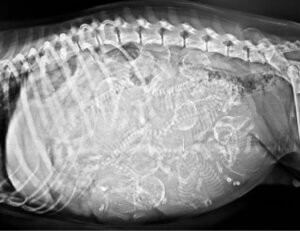

Le 6 février 2021, un chien cyclope est né aux Philippines (Aklan), comme l’indique le journal numérique TimesNoNews. La mère de l’animal a donné naissance à 2 petits, l’un tout à fait normal et l’autre avec la mutation céphalique décrite antérieurement. Comme vous pouvez l’imaginer, l’histoire du deuxième n’est pas très encourageante.

L’apparence du chiot ne pouvait être plus atypique : avec une fourrure blanche et de petite taille, ce chien avait un énorme œil sur son front et 2 grandes langues saillantes de chaque côté de la bouche. Comme l’appareil oculaire prenait beaucoup de place, la structure céphalique du chiot ne présentait aucun museau.

Malheureusement, ce chiot a eu beaucoup de mal à respirer dès sa naissance. Le maître du chien l’a donc conduit chez le vétérinaire, espérant qu’il récupérerait avec un traitement approprié. Comme nous pouvons l’imaginer, le chiot a fini par mourir en raison de difficultés respiratoires, vers 22 heures le même jour.